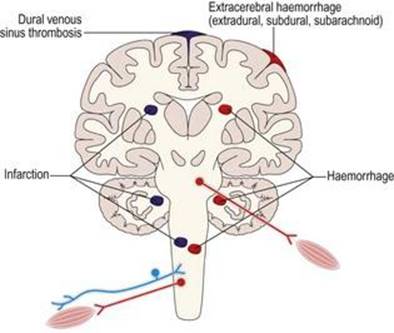

اختلالات عروقی

اختلالات عروقی (شکل ۱.۳۳) به چند روش به گردش خون در سیستم عصبی آسیب میرساند:

انسداد عروق (ترومبوز)

محدودیت تامین خون و اکسیژن (انفارکتوس)

خونریزی در بافتهای عصبی (خونریزی).

شکل ۱.۳۳ اختلالات عروقی سیستم عصبی عضلانی.

شکل ۱.۳۳ اختلالات عروقی سیستم عصبی عضلانی.

رشد سریع ضایعه عروقی را سکته مینامند. تورمهای مادرزادی شریانها (آنوریسم) یا تومورهای عروق خونی (آنژیوم) میتوانند اعصاب جمجمه و خود مغز را تحت فشار قرار دهند. بررسی اختلالات عروقی با هدف حذف اختلالات انعقادی غیرطبیعی در گردش خون، آزمایش دریچهها و عضلات قلب (اکوکاردیوگرافی، الکتروکاردیوگرافی و آنژیوگرافی قلب) و نمایش عروق گردن و مغز توسط آنژیوگرافی انجام میشود. درمان اختلالات عروقی ممکن است خونی یا قلبی باشد و ممکن است به جراحی قلب یا شریانهای گردن و جمجمه نیاز داشته باشد.